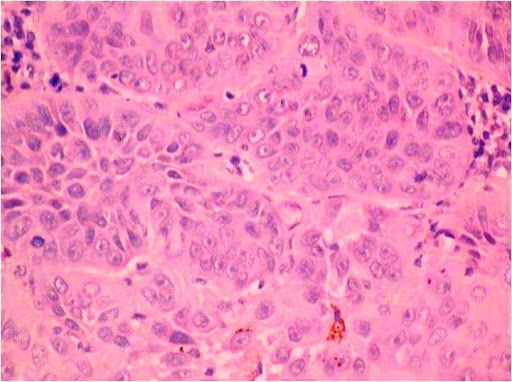

Basaloid squamous cell carcinoma (BSCC), as defined by the World Health Organization, is an aggressive, high-grade variant of squamous cell carcinoma (SCC), composed of both basaloid and squamous components.[18],[19] BSCCs are common in the oropharynx but rare in the oral cavity.[20],[21] Clinically, they present as indurated masses with central ulceration.[21],[22] Histopathologically, they may resemble the solid variant of adenoid cystic carcinoma (ACC), adenosquamous carcinoma, and small cell neuroendocrine carcinoma (SCNC).[21],[22],[23],[24],[25] BSCC can be differentiated from ACC on the basis of myoepithelial cells and basement membrane-like material (both of which are found in ACC but absent in BSCC). Moreover, the atypia in ACC is less pronounced in comparison to BSCC (Figure 3).[23]-[25]

Figure 3. Infiltrating islands of basaloid cells with hyperchromatic nuclei (Hematoxylin and eosin stain x40).

Immunohistochemically, the basement membrane-like material in ACC shows positive expression for laminin and type IV collagen. P63 shows a diffuse positive expression for the tumor cells of BSCC, but is weakly expressed in ACC.[24] Adenosquamous carcinoma shows true ductal acinar differentiation and mucicarmine positivity.[23],[25],[26],[27] BSCC does not show these features and can thus be differentiated from adenosquamous carcinoma.[24],[26]-[27] On the other hand, SCNC shows nuclear molding, hyalinization and crushing artifacts on H&E, and immunohistochemically, shows positive expressions for chromogranin and synaptophysin. BSCC is devoid of all of these features.[23]-[24]-[26] Wain’s criteria[27] is an essential parameter to diagnose BSCC. This criteria include both histologic (peripheral palisading associated with SCC, high nuclear-cytoplasmic ratio, high mitotic index, solid growth pattern) and immunohistochemical features (positive expression for anti-34BE1 and cytokeratin 5/6; negative expression for synaptophysin and chromogranin, and Ber-EP4). Occurrence of BSCC in the oral cavity is infrequent and very few case reports were found in the literature.[22]-[23],[26]